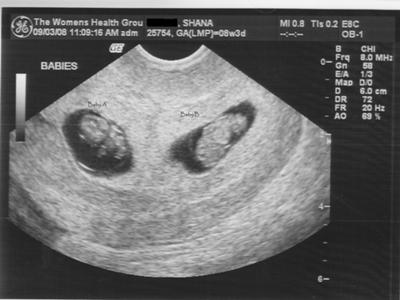

Фотографии на ранних этапах беременности

Раздел: Визуальный дайджест